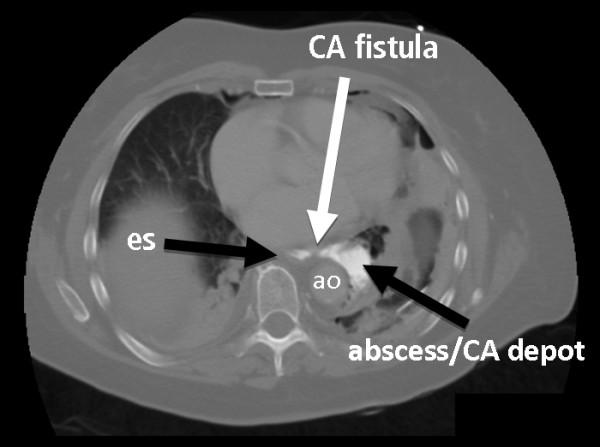

A 73-year-old Caucasian woman was scheduled to undergo elective colonoscopy. For the colonoscopy preparation at home she received commercially available bags containing soluble polyethylene glycol powder. No anti-emetic medication was prescribed. After drinking the prepared solution she had to vomit excessively and experienced a sudden and intense pain in her back. An immediate computed tomography (CT) scan revealed a rupture of the distal esophagus (Boerhaave syndrome). After initial conservative treatment by endoluminal sponge vacuum therapy, she was taken to the operating theatre and the longitudinal esophageal rupture was closed by direct suture and gastric fundoplication (Nissen procedure). She recovered completely and was discharged three weeks after the initial event.

一名73岁的白人女性计划接受择期结肠镜检查。在家中进行结肠镜检查准备时,她服用了市售的装有可溶性聚乙二醇粉末的袋子。未开具止吐药物。饮用准备好的溶液后,她开始过度呕吐,并突然感到背部剧烈疼痛。立即进行的计算机断层扫描(CT)显示远端食管破裂(Boerhaave综合征)。在通过腔内海绵真空疗法进行初步保守治疗后,她被送往手术室,通过直接缝合和胃底折叠术(nissen手术)闭合了食管纵向破裂处。她完全康复,并在初次发病三周后出院。